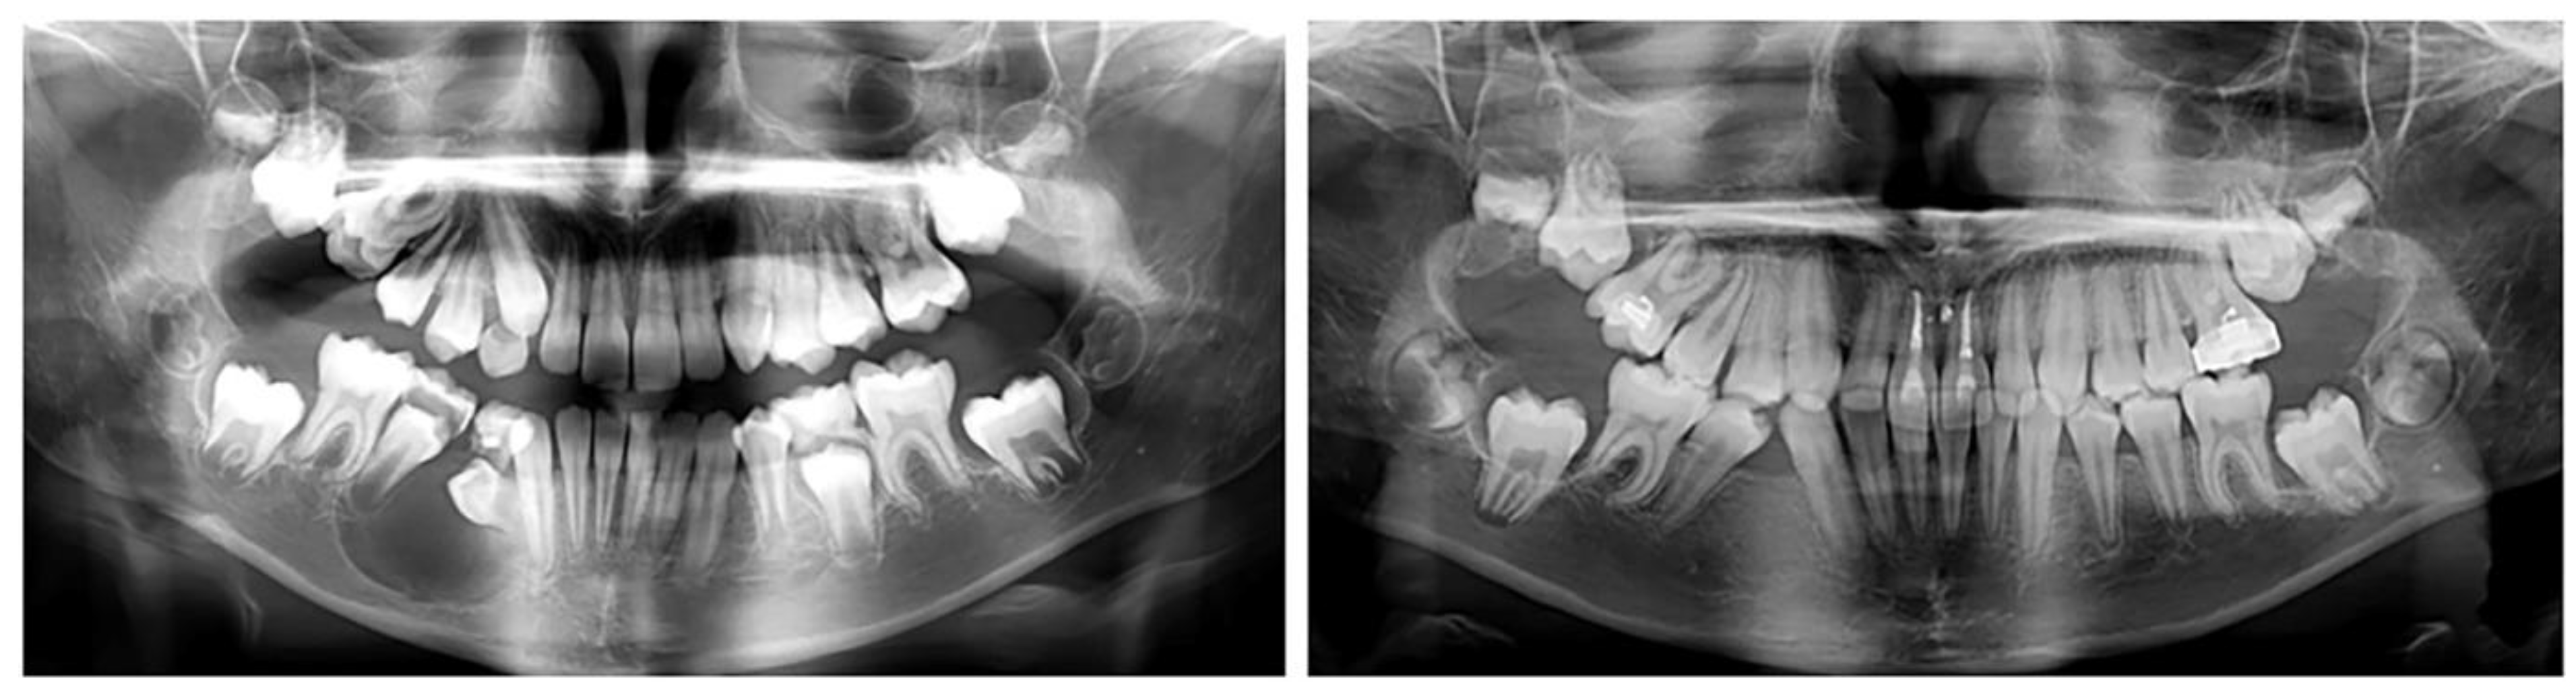

2.2.1 We present an 8-year-old girl with an ectopic eruption of the lower right lateral (42) in the area of the first temporary molar. In the lower dental arch, the temporary right lateral and canine are with preserved positions. After an X-ray examination, hypodontia of the upper laterals was established in the upper dental arch. The well-developed and normally positioned germ of right canines and premolars in the lower were found (Figure 1). In this early phase of mixed dentition, the ectopically placed lower right lateral should be positioned in its normal location. This will prevent future canine transposition or canine retention due to the mechanical barrier that the lateral presents. At the same time, it is important to preserve the perimeter of the dental arch, in the earlier exfoliation of the temporary canine.

Figure 1. Oral clinical status and x-ray examinations of a patient with an ectopic eruption of the lower right lateral (42) in the area of the first temporary molar.